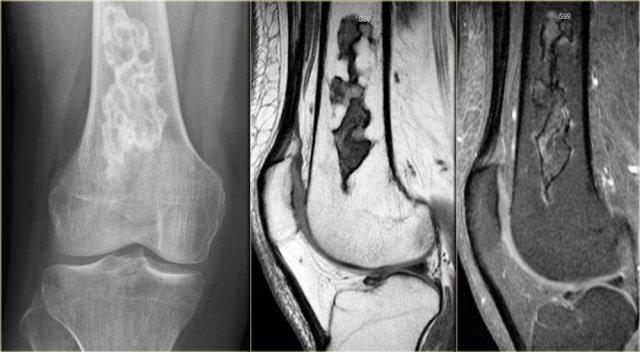

Hình ảnh cho thấy một tổn thương vôi hóa ở đầu gần xương chày mà không có đặc điểm đáng ngờ.

Đây rất có thể là một u sụn nội xương (enchondroma).

Có những đặc điểm khác ủng hộ chẩn đoán sarcoma sụn độ thấp như xạ hình xương dương tính và hình ảnh xói mòn nội màng xương trên MRI (không hiển thị).

Sarcoma sụn đã được chẩn đoán qua sinh thiết.